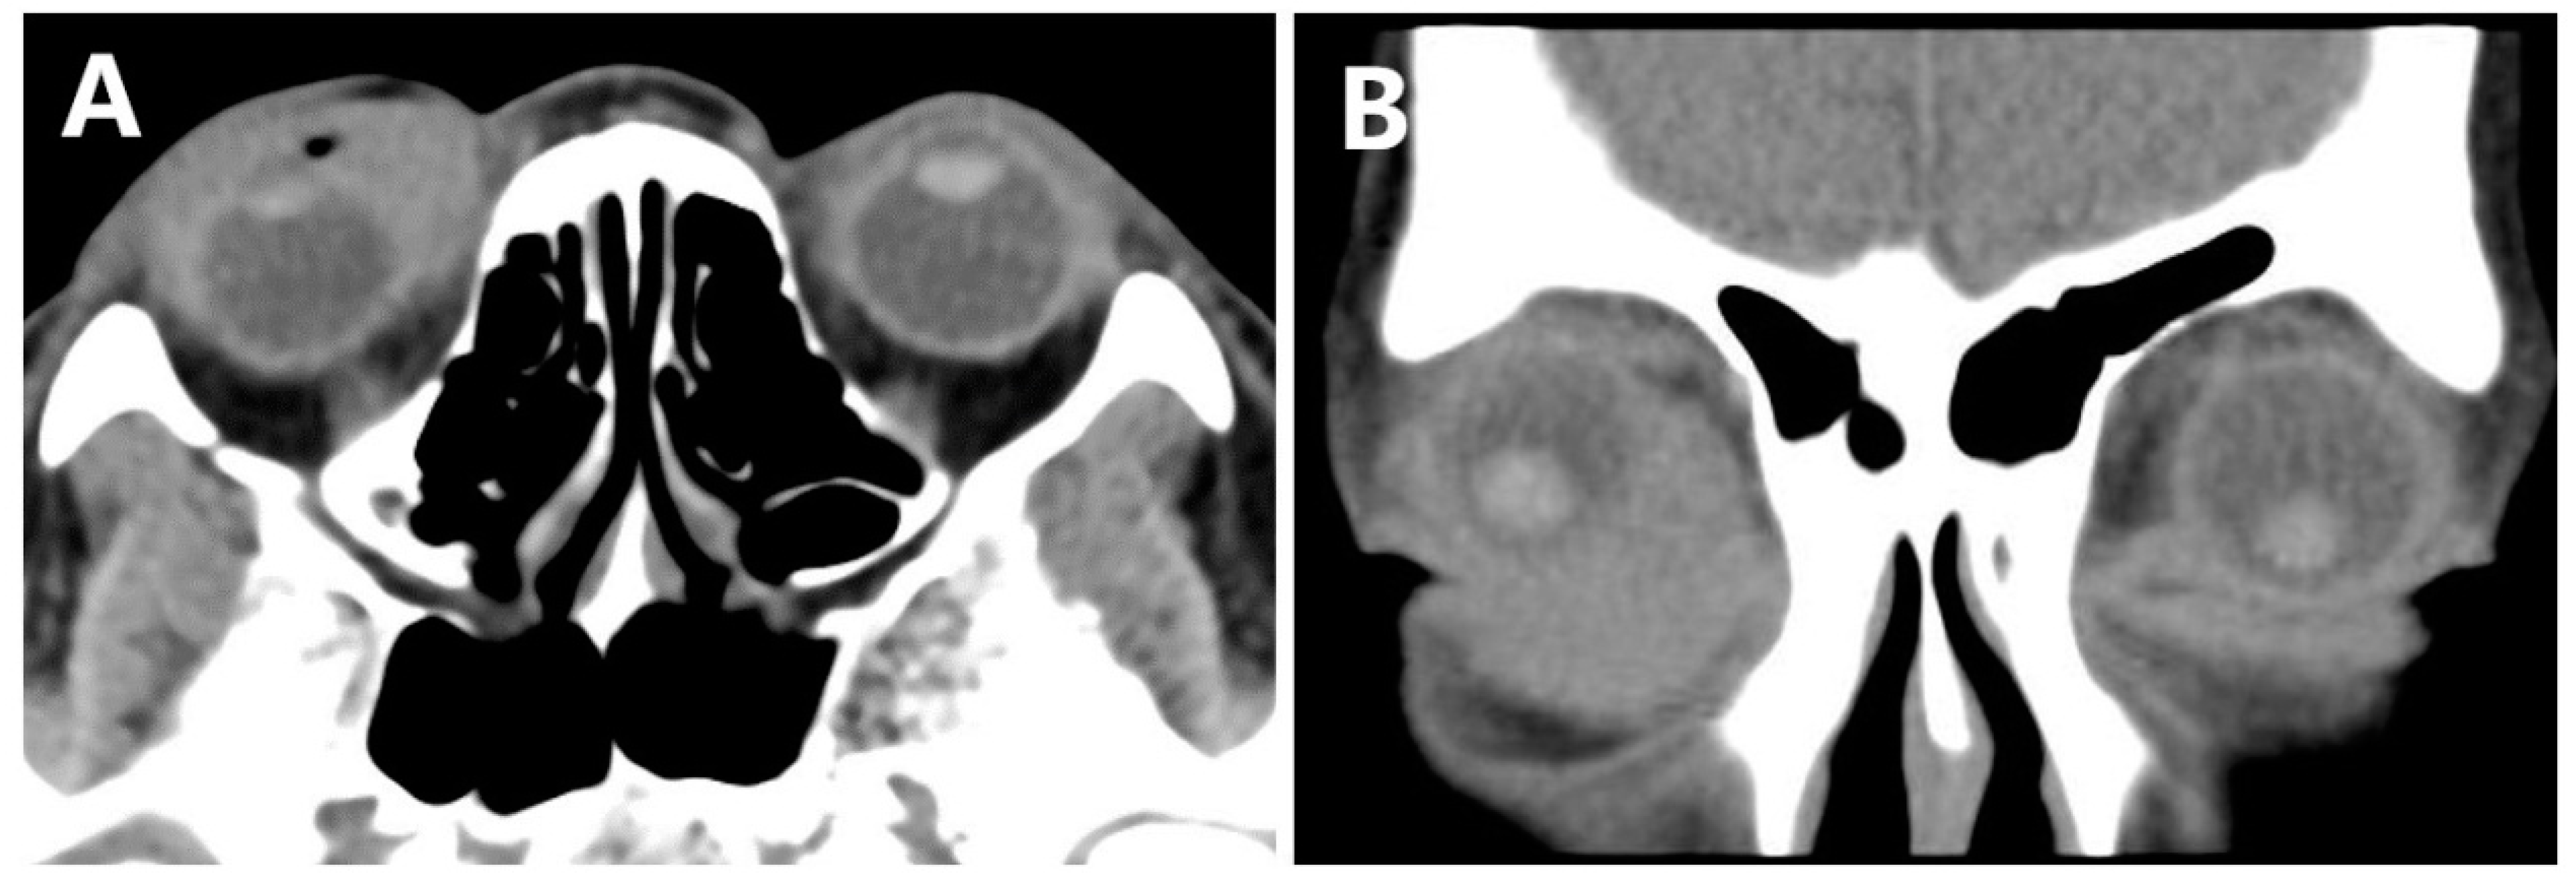

2. Case Presentation